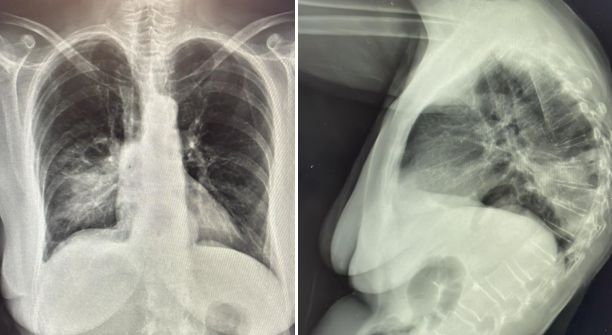

Además de realizar analítica, antigenuria, hemocultivos y gasometría venosa con lactato, solicitamos una RX Tórax PA y Lateral que confirma nuestro diagnóstico.

Inicialmente nuestro diagnóstico diferencial estaba entre varias patologías de origen abdominal como gastroenteritis, pielonefritis o colecistitis, pero ante la exploración física de la paciente, cambiamos nuestro enfoque diagnóstico hacia una neumonía.